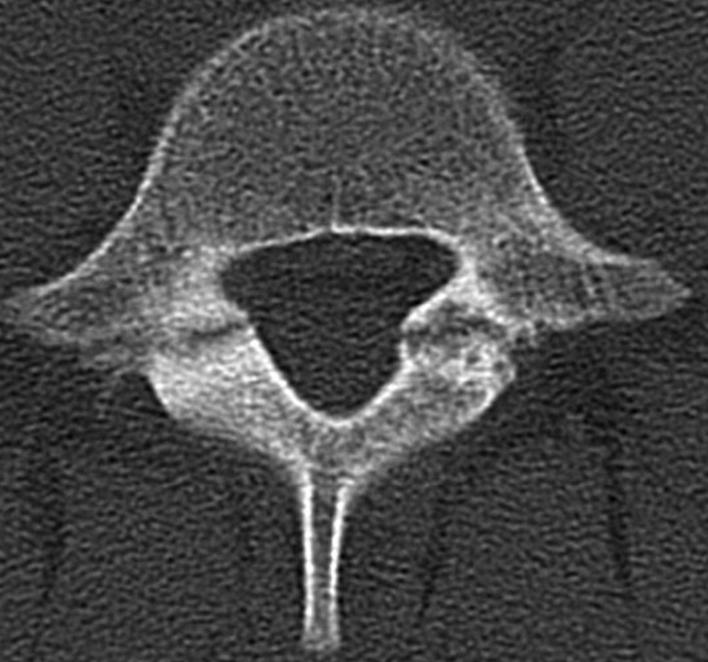

• CT

• inidcations

• best study to delineate anatomy of lesion

• findings

• pars stress reaction will show up as sclerosis on x-rays and CT scan

• best study to diagnose and delineate anatomy of pars defect